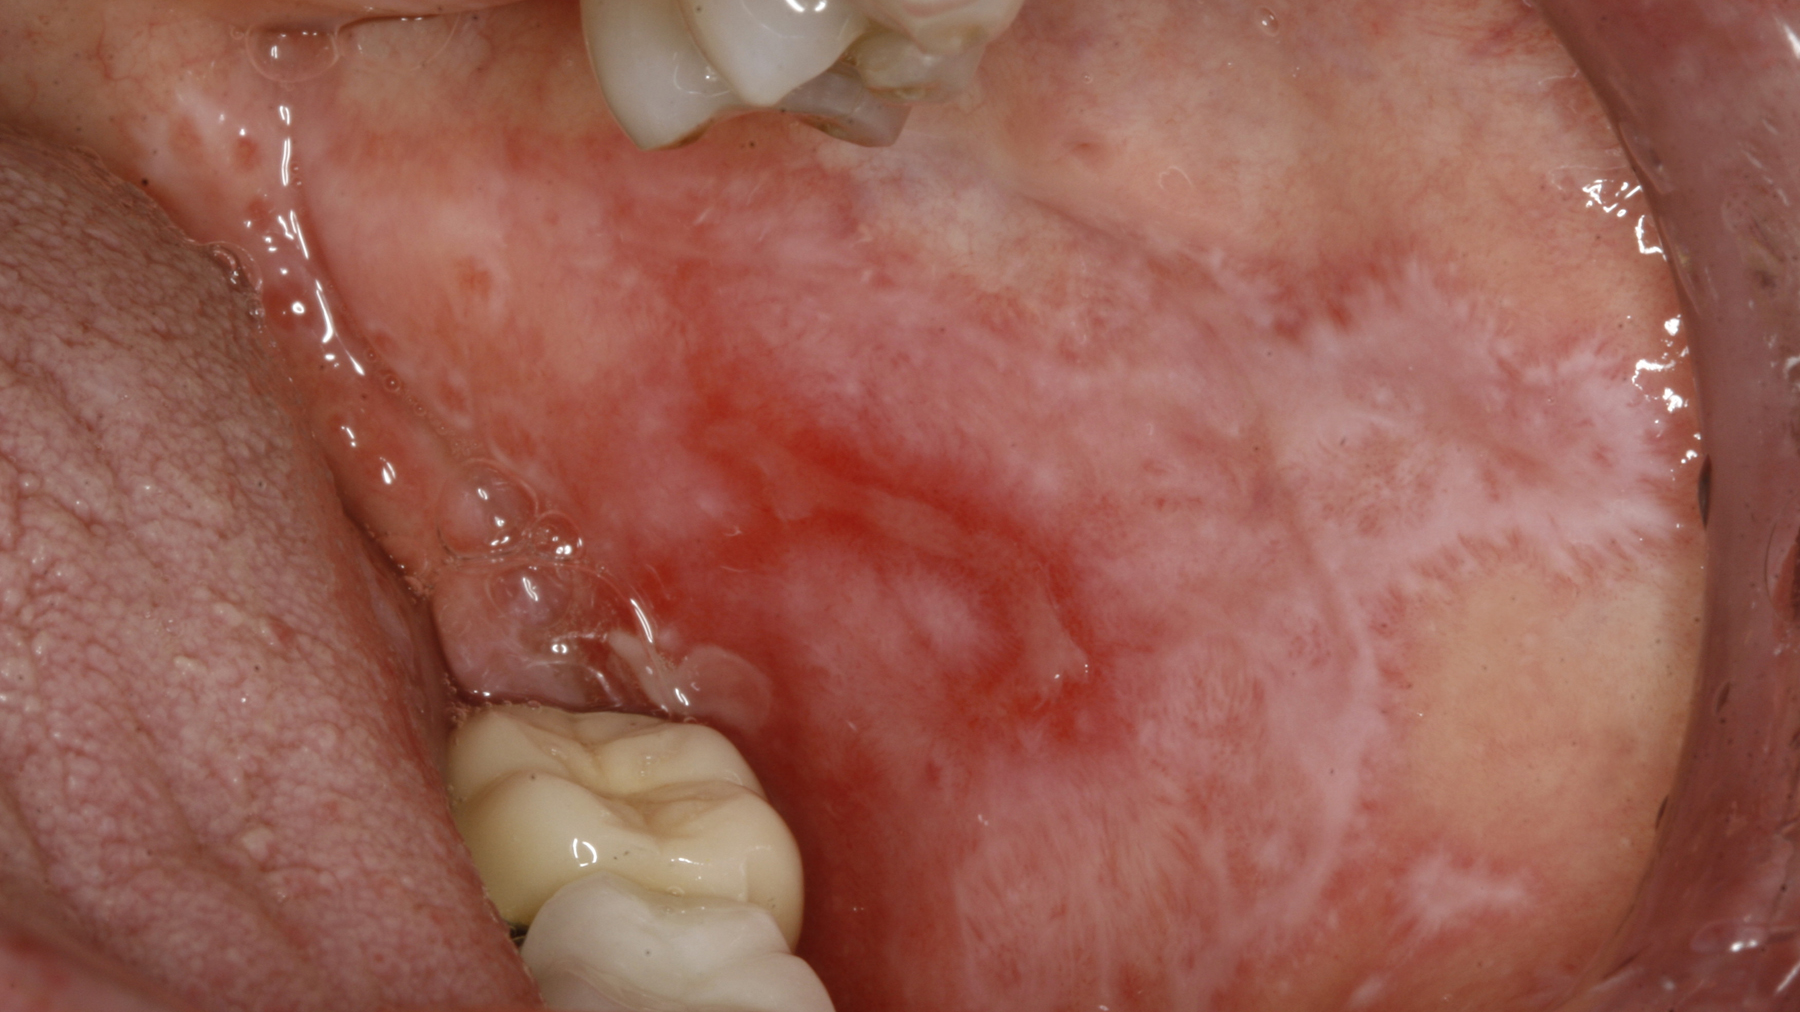

A healthy, 54-year-old, white female presents for evaluation of a painful area on her left and right buccal mucosa.

She reports a whitish-red area bilaterally that is tender to the touch. She states it came up slowly over the last two weeks and nothing seems to make it better. She denies weight loss, fatigue, recent dental work, or trauma in both areas, and there are no extraoral manifestations of these symptoms.

Upon clinical exam, the buccal mucosa bilaterally is erythematous and atrophic, very tender to palpation. There is no cervical lymphadenopathy, and the rest of the oral exam in within normal limits.

LP is divided into two categories: the reticular form and the erosive form.1 The reticular form is more common than the erosive form. Typically, the reticular form is asymptomatic to the patient. Clinically, it is characterized by a white, lacy latticework of mucosa found on the buccal mucosa, attached mucosa, and tongue. These white striae of mucosa are referred to as Wickham striae. The erosive form, as outlined in the above vignette, is the more symptomatic form of LP. It is typically characterized by painful, atrophic, ulcerated areas of the oral mucosa.2

Diagnosis of this condition is dependent on the form of LP the patient presents with. The reticular form is usually made on the basis of a clinical presentation. An incisional biopsy can also be performed, or treating the area empirically with a topical corticosteroid and ensuring resolution of the lesion after two to three weeks can aid the clinician in being sure of his or her diagnosis. When the area in question is suspected to be erosive lichen planus (ELP), a biopsy of the lesion is typically advised, not only to ensure the area is in fact ELP, but to rule out dysplasia or a malignancy.